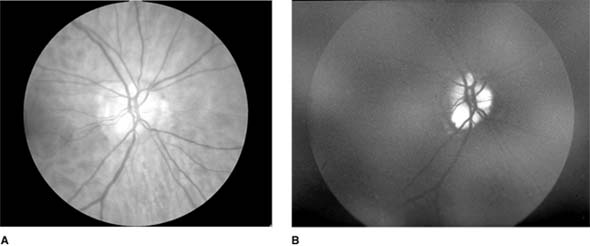

Figure 14-13

Figure 14-13: Pseudo-Foster Kennedy syndrome due to sequential anterior ischemic optic neuropathy. A: Swollen right optic disk with hemorrhages due to current ischemic episode. B: Atrophy of left optic disk due to previous ischemia. C: Early phase of fluorescein angiogram of right eye showing poor perfusion of optic disk and dilated superficial disk capillaries. D: Late phase of fluorescein angiogram showing disk leakage.